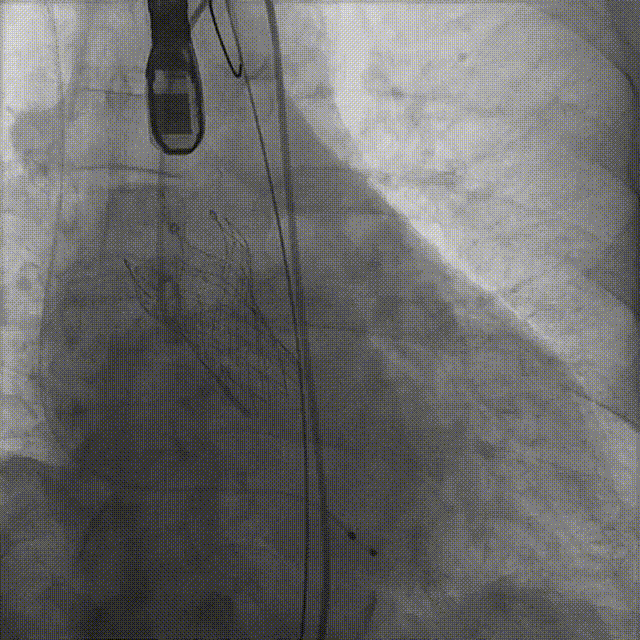

病例概览

患者病史 体检发现心脏瓣膜病半月余,平素无症状 ,有高血压病史。 后来院复查诊断为:主动脉瓣狭窄(重度)、先天性主动脉瓣二叶瓣畸形、心室肥厚、升主动脉扩张心功能 I 级(NYHA 分级)、高血压病 2 级(极高危)。 术前 CT:Type0型二叶瓣,瓣叶增厚,无钙化,类风湿性;瓣环径25.6mm,LVOT稍收窄,瓣环水平夹角66.6°,轻微横位心;左右冠开口高度可,瓣叶不长,无冠脉风险;心室收缩末内径约32mm,室壁增厚;外周入路无明显迂曲,无钙化、双侧内径可、双股中分叉,右侧为主入路能够支持20F大鞘通过。 造影角度及入路:LAO 6° CAU 13° 手术策略 采用右侧股动脉为主入路,左侧为辅助入路,常规穿刺。推荐使用20球囊预扩,预装TAV29瓣膜,初始定位对齐瓣环上0mm开始释放。 手术过程 20号球囊预扩无明显腰征 输送器过弓跨瓣顺滑 80%工作位观察 术后造影,瓣膜释放位置良好,无瓣周漏 术后超声:人工生物瓣释放后形态满意,瓣叶开放、关闭活动良好,无瓣周漏;跨瓣血流速度降至 2.5m/s,平均压力梯度6mmHg,符合手术预期。 Prostyle A®预装干瓣——“刚柔并济”助力临床最优化解决方案: 丝滑过弓能力:Prostyle A®短瓣架设计联合远端超滑亲水涂层,即使没有联合使用snare,都可以柔顺过弓,该例横位心的患者更好的展现了输送系统的柔顺性; 平衡的径向支撑力:该例患者Type0型二叶瓣,术后形态展开良好且无瓣周漏,在横位心等复杂情况下实现稳定锚定。 80%可回收设计:80%工作位观察,起搏时间更短,对患者损伤减少到最小,也利于术中精准调整瓣膜位置,保证术后效果。